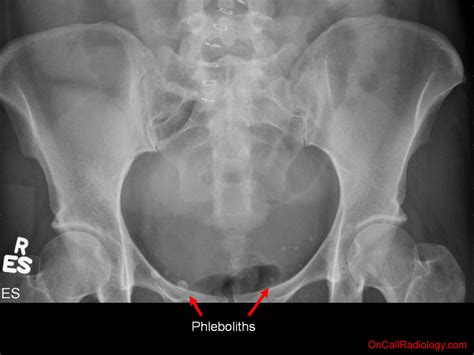

Phleboliths are small, calcified deposits that form within veins. They are typically composed of calcium and other minerals and can vary in size from a few millimeters to several centimeters. These deposits are often incidental findings during imaging studies, such as X-rays, CT scans, or MRIs. While phleboliths can occur in various parts of the body, their presence in the pelvis is particularly noteworthy due to the anatomical complexity of the region.

• X-Rays: Plain radiographs can sometimes detect phleboliths, especially if they are large enough. However, X-rays are less sensitive compared to other imaging modalities.

• Incidental Findings: Many phleboliths are discovered incidentally during imaging studies performed for other reasons. In such cases, they are often benign and do not require any intervention.